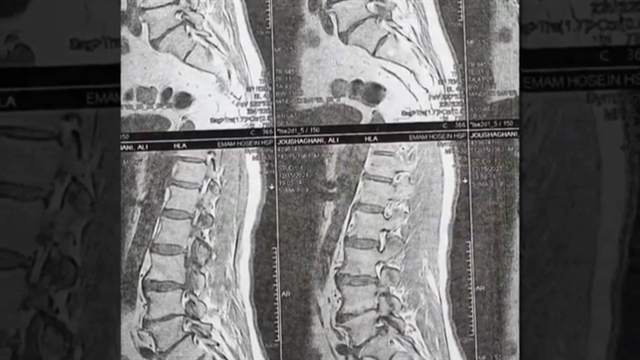

آقای ۶۰ ساله با درد شدید کمری ؛ ناتوانی در راه رفتن